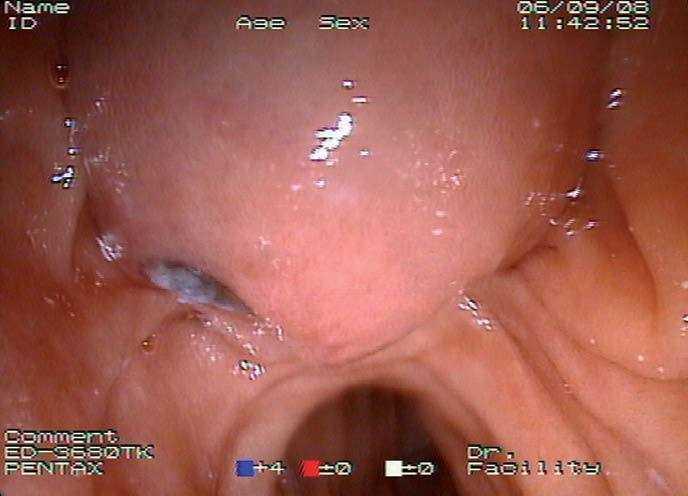

Mujer de 87 años que ingresa en el servicio de cirugía por ictericia, colangitis y pancreatitis aguda. Se instauró tratamiento con sueroterapia y antibióticos, que consiguió la estabilización hemodinámica de la paciente. En una colangiopancreatografía por resonancia magnética (fig. 1) se observó un defecto de repleción en el colédoco distal. Con la intención de desobstruir la vía biliar, se realizó una colangiopancreatografía retrógrada endoscópica (CPRE), empleando sedación consciente con midazolam y dolantina. En la endoscopia, la ampolla de Vater se encontró muy abultada, con un orificio en el que parecía entreverse una coledocolitiasis (fig. 2). Se realizó una esfinterotomía biliar amplia (fig. 3) y se extrajo una coledocolitiasis de 13 mm de diámetro máximo, que estaba impactada en la ampolla (fig. 4). La evolución de la paciente fue satisfactoria.

Fig. 2